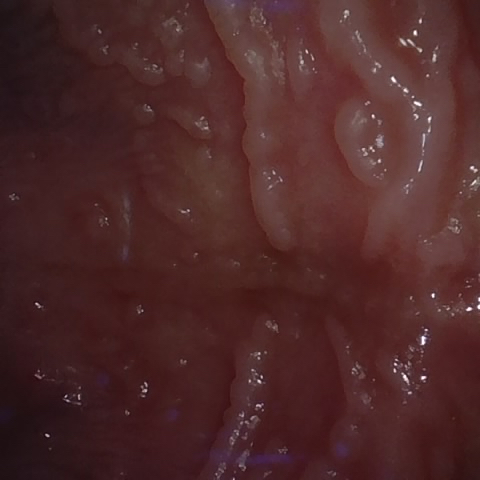

Annotated as "Good"